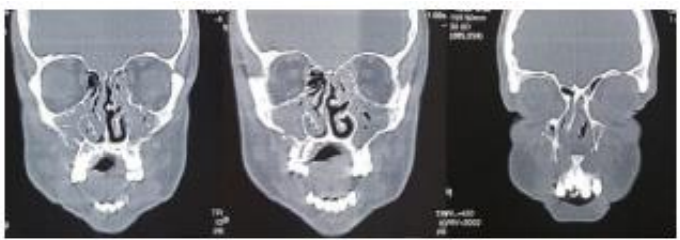

M.A., 32 anos, é atendido no Pronto Atendimento do Hospital Regional, vítima de colisão auto-moto. Ao exame físico: Desorientado, Pupilas Isocóricas e com reflexos pupilares preservados, edema de face, múltiplas escoriações, hematomas na região frontal e malar bilateral, afundamento do dorso nasal, epistaxe bilateral, ao exame da cavidade oral: fratura dos incisivos centrais superiores e presença de mobilidade da maxila. A partir dessas informações e após a análise do seguinte exame de imagem abaixo, assinale a alternativa que contém o diagnóstico: